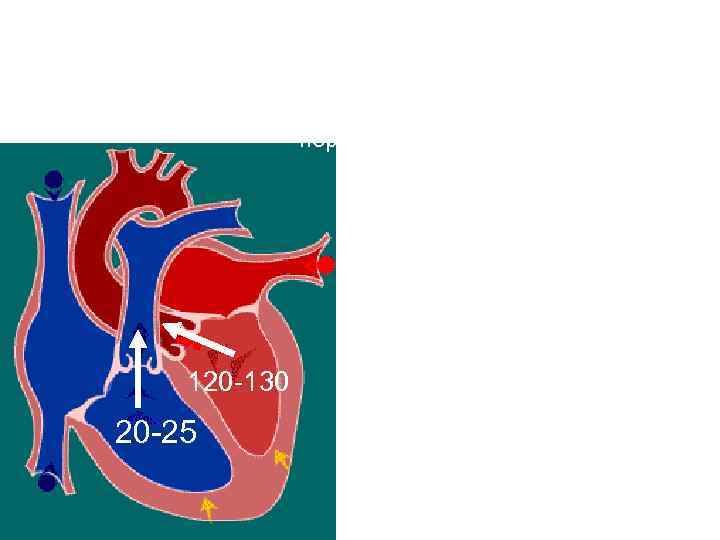

Систола желудочков Фаза изгнания период быстрого изгнания Клапаны: створчатые - закрыты полулунные – открыты Давление в желудочках: -правом – 20 -25 мм рт. ст - левом – 120 -130 мм рт. ст 120 -130 20 -25 Гемодинамика: 2/3 систолического объема выбрасывается в аорту и легочный ствол

Систола желудочков Фаза изгнания период быстрого изгнания Клапаны: створчатые - закрыты полулунные – открыты Давление в желудочках: -правом – 20 -25 мм рт. ст - левом – 120 -130 мм рт. ст 120 -130 20 -25 Гемодинамика: 2/3 систолического объема выбрасывается в аорту и легочный ствол